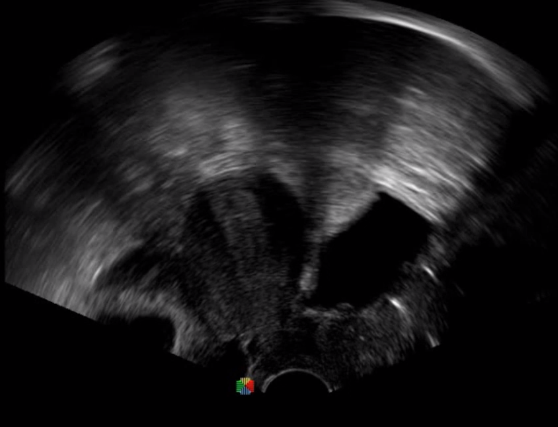

5   TEE

TEE(經(jīng)食道超聲心動圖)將超聲探頭置入食道內(nèi),從心臟的后方向前近距離探查其結(jié)構(gòu) ,克服了經(jīng)胸超聲檢查的局限性,避免肺內(nèi)氣體、胸壁脂肪、胸廓畸形等因素影響,觀察角度更多,圖像更加清晰,測量數(shù)據(jù)更準確。

經(jīng)食道超聲 大動脈短軸